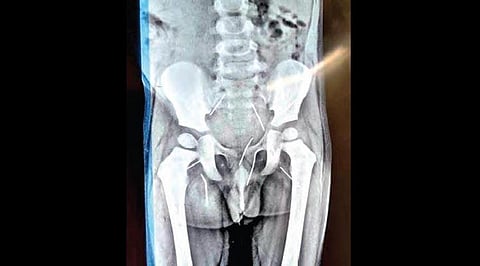

X-ray of a three-year-old boy’s body in which as many as 11 needles were found on Tuesday.

When Loknath was taken to a private hospital in Wanaparthy for scanning, doctors found not one or two, but as many as 11 needles under his waist, close to his kidneys. The doctors tried to remove some needles which could be seen protruding through his anus.